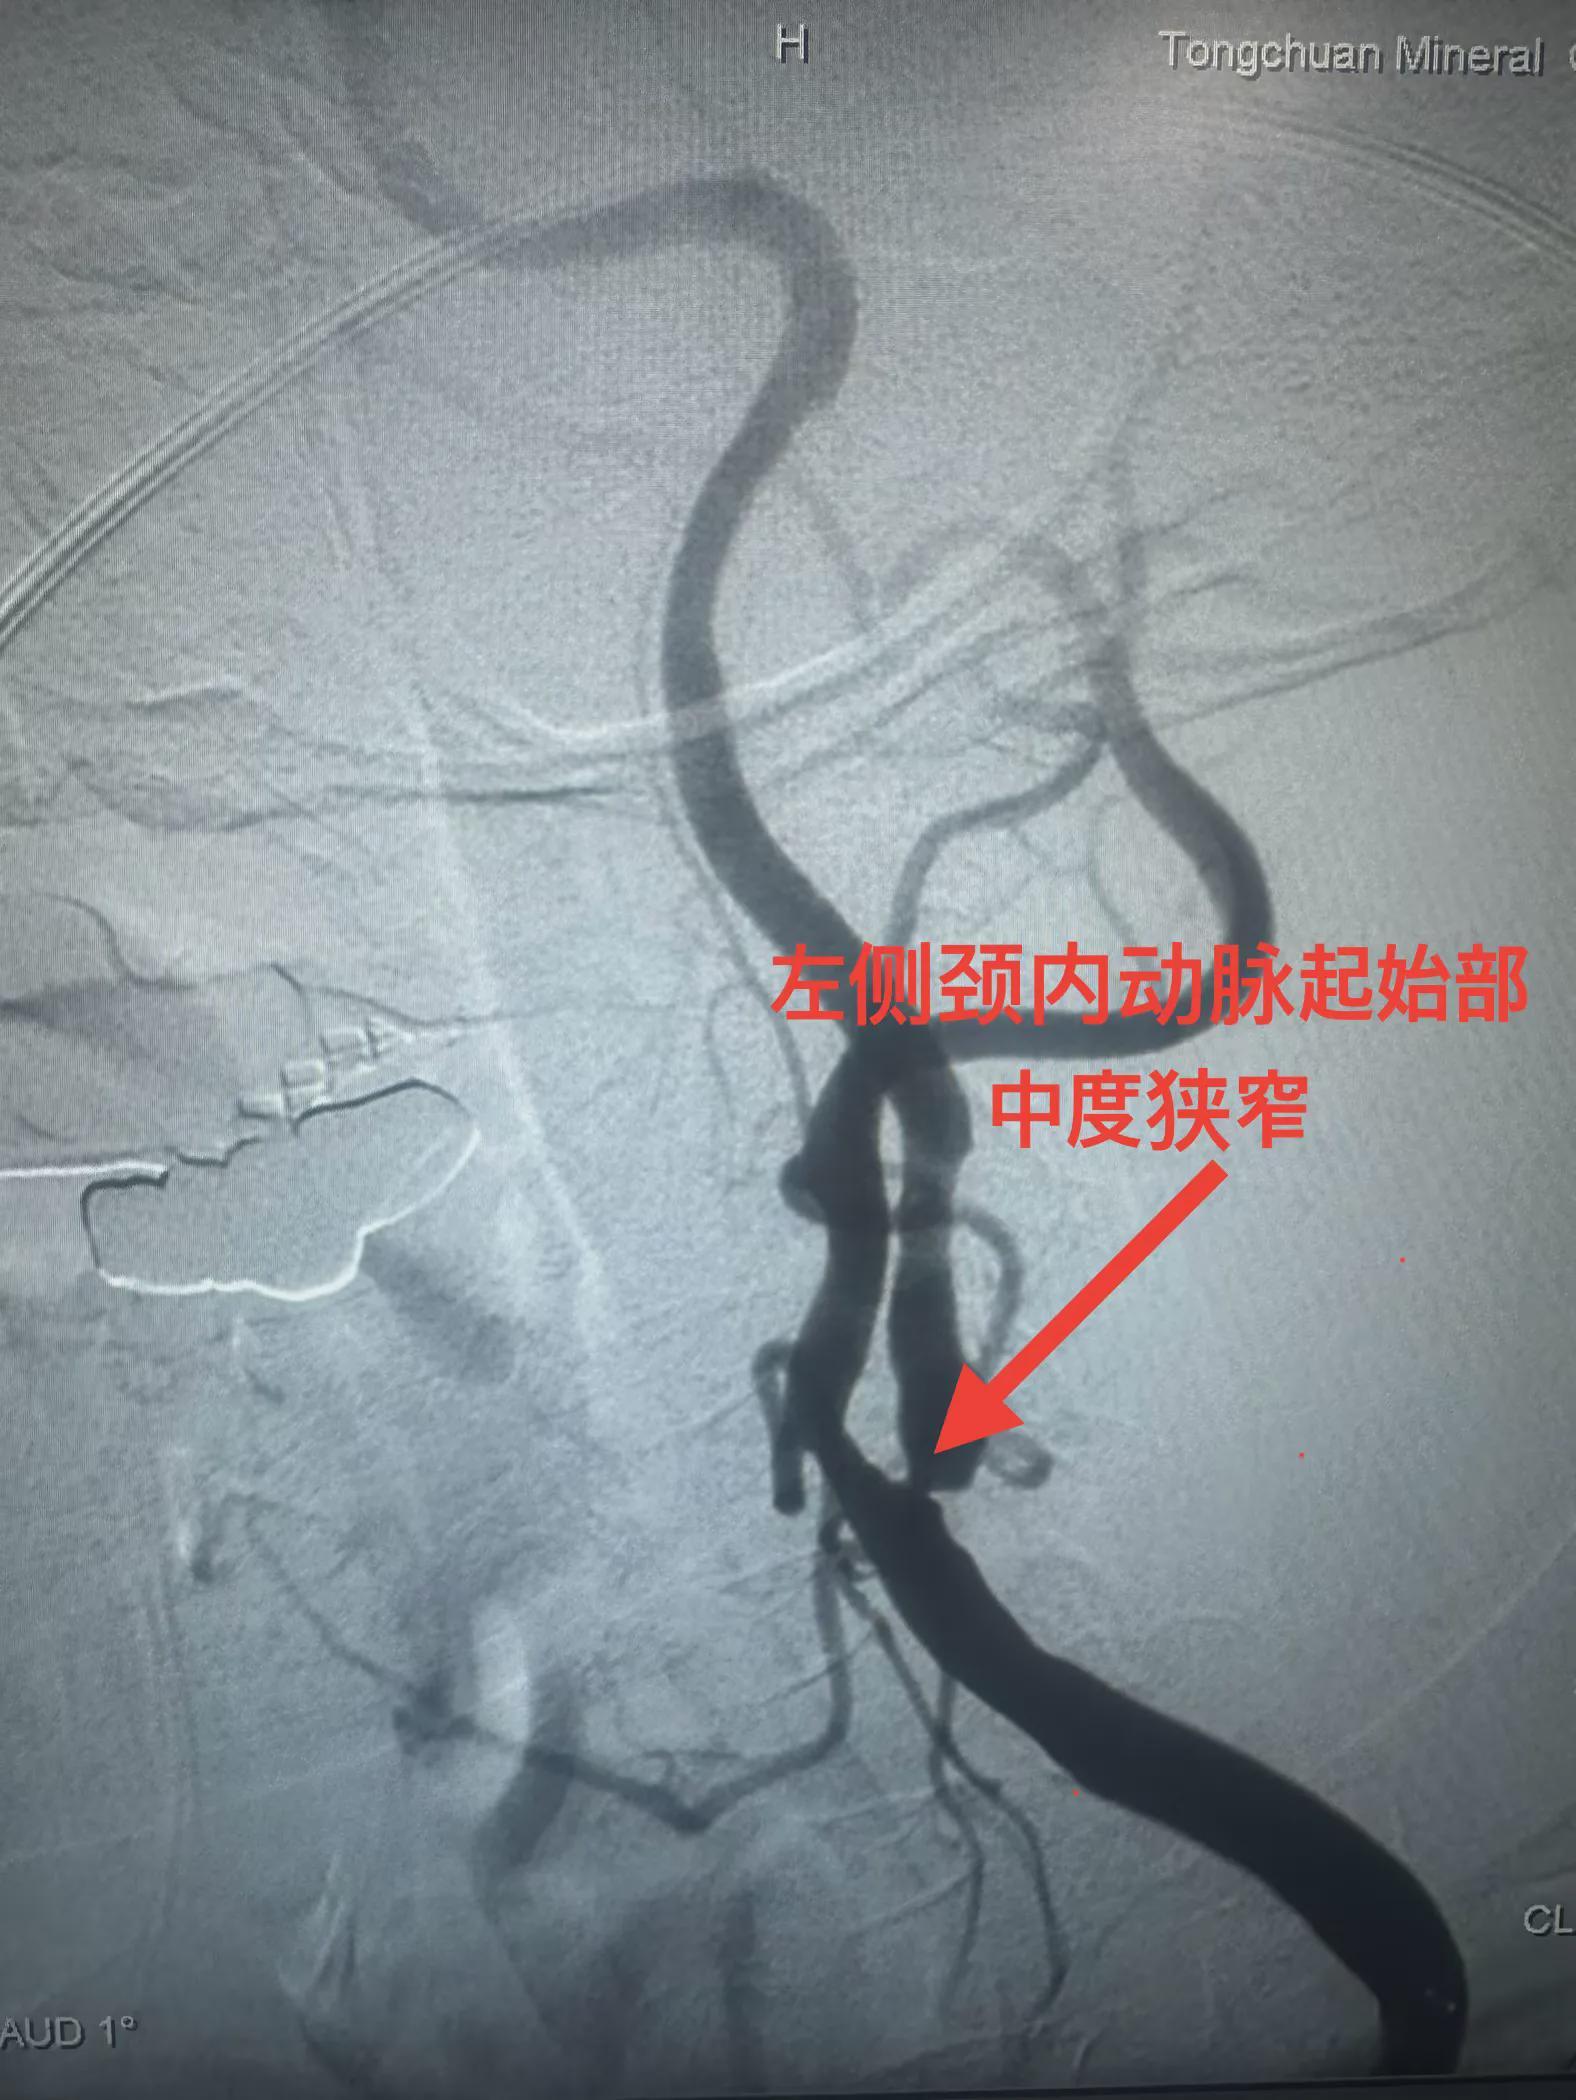

患者系77岁女性,因发作性言语不清、右侧肢体无力6小时入院。入院后,行核磁共振检查提示多发性陈旧脑梗,并进一步行全脑血管造影,显示左侧颈内动脉起始部中度狭窄。考虑到患者病情特点,铜川矿务局脑血管首席专家兼卒中中心名誉主任李健教授和学科带头人邵元主任决定带领团队采用OCT技术进行辅助支架植入治疗。